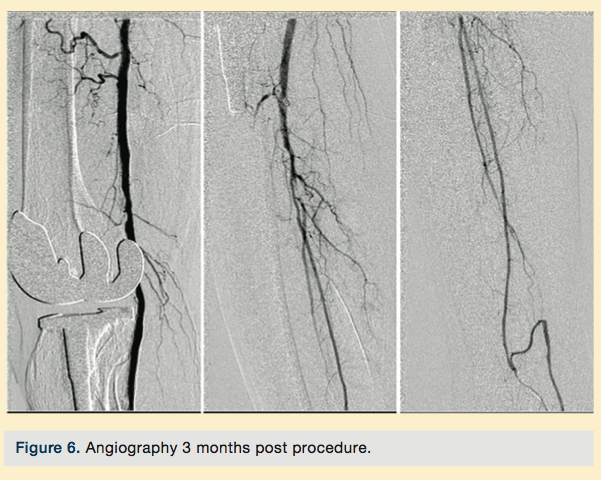

Peripheral angiography showed total occlusion of the right distal superficial femoral artery extending into the popliteal artery and into the trifurcation, with reconstitution of a peroneal and a posterior tibial. We attempted to obtain antegrade access to the lesions of the right infra-popliteal vessels (Figure 1). After failing to cross the lesion, we obtained retrograde access, puncturing from below the lesion through the posterior tibial artery near the ankle joint (Figure 2). Access was obtained and the lesion below the knee was crossed (Figure 3). Following this, the V-18 control wire (Boston Scientific) was snared from above, a CXI support catheter (CSI) was backloaded over the wire, and an antegrade Viperwire (CSI) was then placed, with removal of the retrograde sheath and wire. Atherectomy was performed with the 1.5mm Stealth 360° orbital atherectomy device (CSI) followed by balloon angioplasty with Cook, Sterling (Boston Scientific), and Chocolate (Cordis) balloon catheters. After angioplasty, significant improvement in luminal gain was noted at the expense of a dissection (Figure 4). We chose to place a Zilver PTX drug-eluting stent (Cook) within the distal superficial femoral and popliteal artery segment (Figure 5). After the procedure, the patient’s wounds completely healed. An angiogram 3 months later was performed, showing the vessels to be widely patent (Figure 6). The patient sent us a video of himself finally walking, and without pain (Video 1; online).